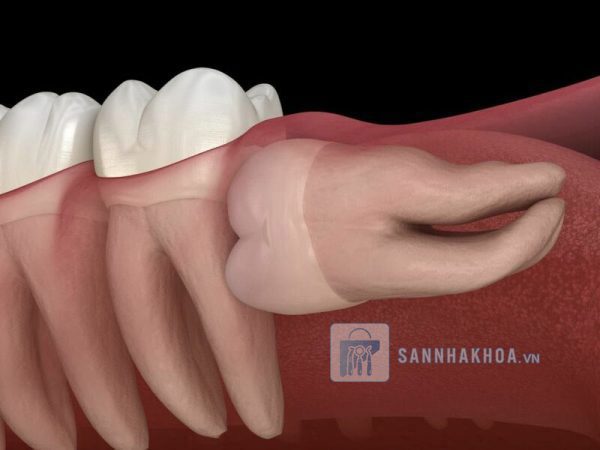

Xô lệch các răng khác: Răng nanh mọc bên dưới thường chèn ép hoặc đẩy lệch các răng lân cận, dẫn đến tình trạng chen chúc hoặc hở răng, ảnh hưởng đến thẩm mỹ và chức năng.

Nguy cơ hỏng răng lân cận: Răng nanh mọc ngầm thường đẩy vào chân răng bên cạnh, làm tổn thương chân răng hoặc thậm chí khiến răng khác lung lay, gãy rụng.

Ảnh hưởng đến răng lân cận: Răng nanh mọc ngầm thường chèn ép chân răng bên cạnh, làm tổn thương hoặc gây xô lệch các răng khác. Nếu không thể điều chỉnh được vị trí của răng, nhổ bỏ sẽ là giải pháp an toàn nhất.